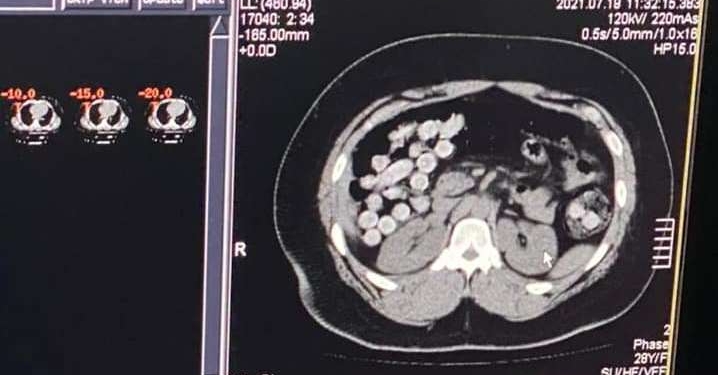

Наркокурьерами оказались двое иностранцев. Один спрятал кокаин в личных вещах, а вот другой – в желудочно-кишечном тракте: смельчак проглотил целый килограмм порошка.